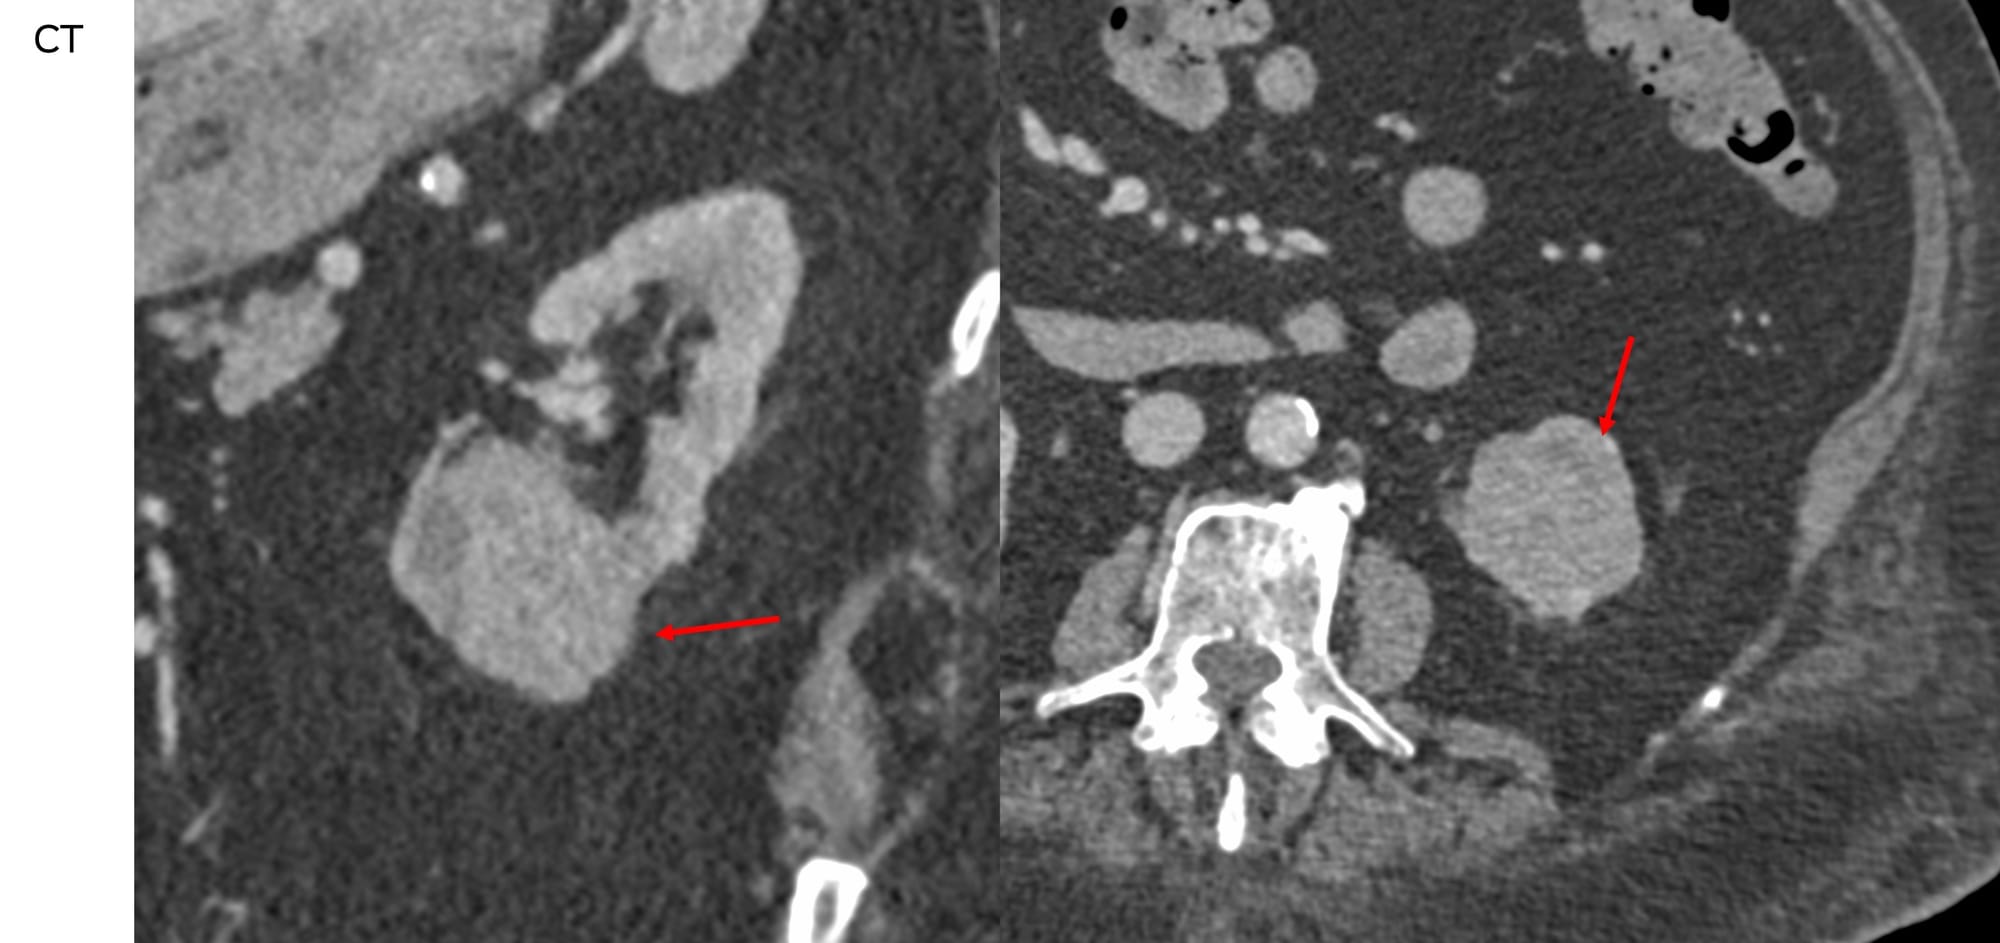

A 75-years old man with multiple comorbidities had a solid renal neoplasm > 4 cm. He and his family decided to go ahead with cryoablation after sifting through all possible options with their urologist and oncologist.